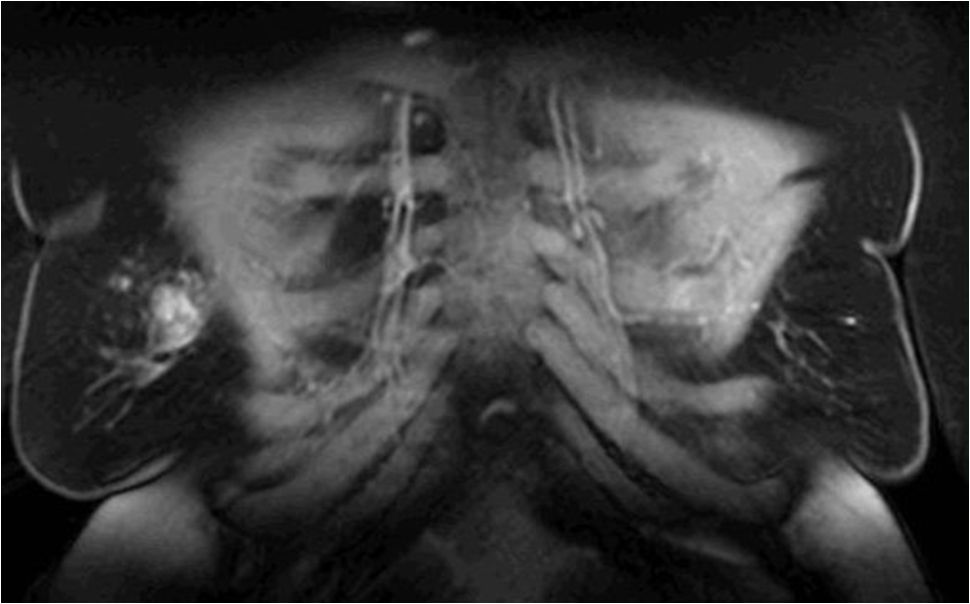

Wie sieht es aus mit der zukünftigen Forschung zum Thema der IM Bestrahlung? Es ist wichtig, international anerkannte Dosisbeschränkungen zu entwickeln, während weiter daran gearbeitet wird, technische Lösungen zu finden, um den therapeutischen Nutzen zu verbessern. Das schließt die Erforschung des potenziellen Nutzens von Protonenstrahltherapie bei jenen Patienten mit ein, bei denen die Therapiepläne selbst mit den besten Photonentechniken nur suboptimal sind.